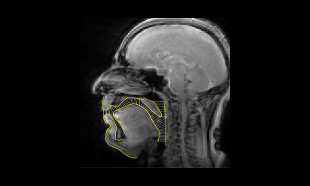

Real-time MRI of the vocal tract